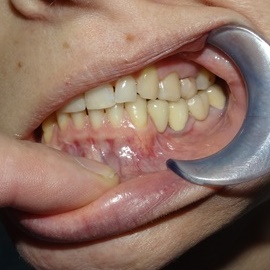

Przedtrzonowce często należą do okolicy estetycznej należy więc zwrócić wzmożona uwagę na poprawną anatomię tkanek kości i dziąsła. Po utracie zęba 25 pacjentka kilka lat chodziła bez jego uzupełnienia, doszło do przesunięcia się zęba 26. U tej pacjentki przed laty był wykonany most jednobrzeżny na czwórce, dość szybko doszło jednak do przeciążenia zęba filarowego, zaniku kości wyrostka i wreszcie pęknięcia korzenia zęba filarowego mostu. Po ekstrakcji i wygojeniu kości stwierdzono ubytek kości wyrostka przekraczający objętość 50% stanu początkowego. Stąd główny nacisk położono na odbudowę tkanek. Uzyskano zadowalający wynik anatomiczny.